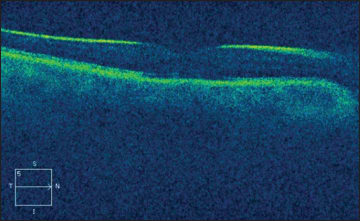

Figure 1. Vitreomacular traction with stage 2 macular hole. Preoperative OCT shows an adherent vitreous still attached to a small bridge of inner retinal tissue, with a small full-thickness macular hole (left). This patient underwent pars plana vitrectomy. By postoperative day one, the hole was noted to be closed (right). This patient did well with vitrectomy, although today an intravitreal injection of ocriplasmin might be an appropriate nonsurgical option to consider as well.

Figure 2. Postoperative day one OCT through a gas-filled eye. This patient had a full-thickness macular hole repaired by pars plana vitrectomy and membrane peel. At the end of the case, the eye was filled with 20% sulfur hexafluoride gas. This OCT, obtained using a Carl Zeiss Meditec Cirrus platform, was taken one day after surgery and demonstrates a closed hole.